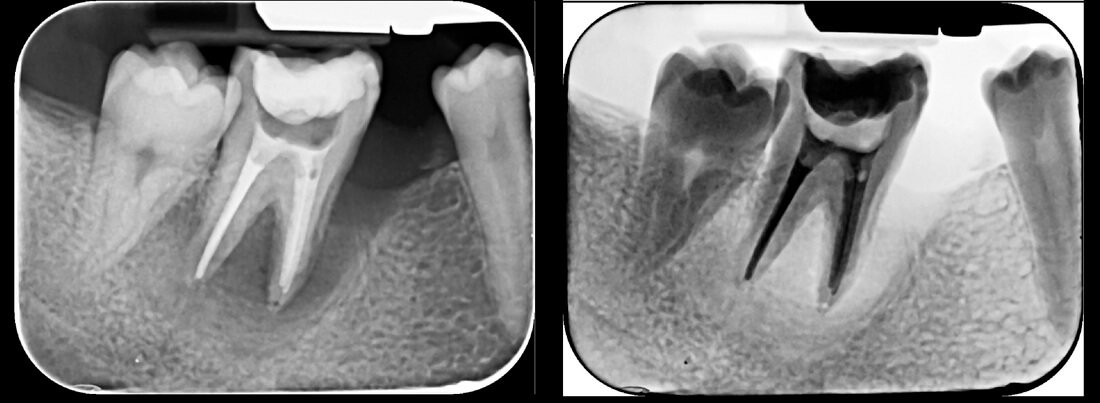

Endodonția este o ramură esențială a stomatologiei, axată pe diagnosticarea, prevenirea și tratamentul afecțiunilor pulpei dentare și a țesuturilor periapicale. Această specialitate joacă un rol crucial în salvarea dinților naturali, evitând extracțiile și menținând sănătatea orală pe termen lung. Prin tehnici avansate și echipamente de ultimă generație, endodonția asigură tratamente precise și eficiente, contribuind la redarea sănătății și funcționalității dinților într-un mod durabil și predictibil.

Utilizarea tehnicilor moderne asigură un tratament rapid, precis și confortabil pentru pacient.

Reconstituirea coronară cu materiale de calitate conferă rezistență pe termen lung.

Tratamentele corecte reduc riscul de infecții și complicații viitoare.